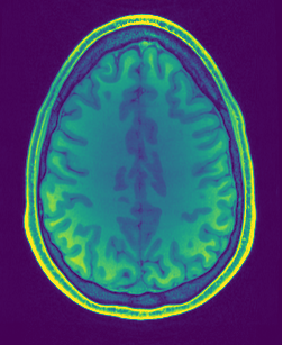

Figure 1: Reconstruction results for R = 3, with (1(a)) the fully sampled image, (b) the zero-filled image, (c) the reconstruction with no bias field estimation, (d) the joint reconstruction with bias field estimation using N4. The first three rows show reconstruction results for an HCP image, its zoomed-in version and the corresponding bias field. The next three rows show results for an in-house measured image. For visualization purposes, MR images are clipped to [0, 1.2] and bias fields, to [0.5, 1.8].

The quantitative improvement is also supported by the visual inspection of the images given in Figure 1. From the HCP image, one can observe that the level of artifacts is reduced with the proposed method. This becomes more evident in the zoomed-in images. The red arrow points to a part of the image where the proposed method can reconstruct the structures faithfully, whereas the baseline method struggles. Aliasing artifacts are globally suppressed better with the joint reconstruction method. Similarly, for the in-house measured image, the grey matter structure that the red arrow points to is not reconstructed in the baseline method, whereas it again appears with the proposed method.